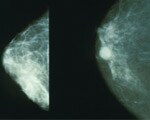

Mammograms given to women under 50 years with a moderate family history of breast cancer can spot cancers earlier and increase the odds for long-term survival.

The study enrolled women from 76 health centres across 34 cancer research networks, 91 percent of whom were between the ages of 40 and 44 years at the start in UK. The women's average age was 42 years, and slightly less than half had a relative with breast cancer diagnosed before they were 40 years old. The researchers examined mammogram results for 6,710 women with several relatives with breast cancer, or at least one relative diagnosed before age 40, finding that 136 were diagnosed with the cancer between 2003 and 2007. About 77 percent of the breast cancer cases diagnosed during the study were detected at screening, giving the early mammograms a 79 percent sensitivity rate. Researchers predicted an 81 percent average 10-year survival rate among participants, while survival rates for those in control groups were forecasted at no more than 73 percent.

These women, who researchers said were probably not carriers of a mutated breast cancer gene, started receiving mammograms at an earlier age than recommended. The findings showed their tumours were smaller and less aggressive than those in women screened at typical ages, and these women were more likely to be alive for 10 years after diagnosis of an invasive cancer.